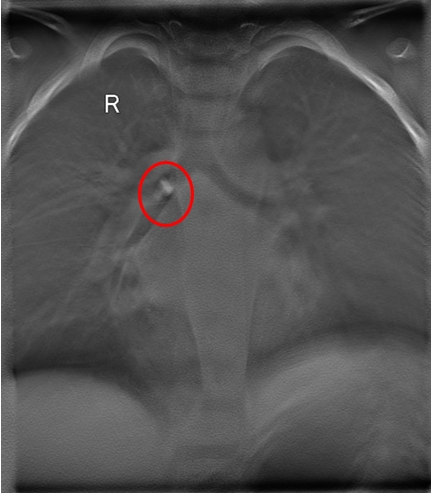

病例一:

![]() 断层融合提示侧支气管分叉处可见一高密度影 |